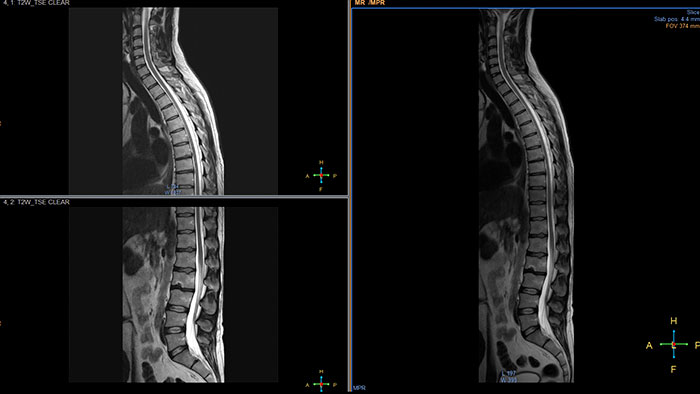

MobiView

MR MobiView

Automatic review of total body MR data

MR MobiView, an option within the Multi Modality Viewer, automatically combines "stitches“ images from multiple acquisitions of the same examination to create one overall volume.

• Key clinical cases are MRA run-offs, whole-body metastases screening from eye-to-thigh, and total spine views to show the complete CNS.

• The resulting image series can be viewed, filmed, and exported using a DICOM compliant tool.